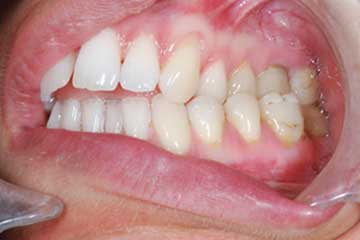

Con protesi fissa superiore e protesi fissa inferiore

I denti irrecuperabili dell'arcata superiore ed inferiore del paziente di anni 65

sono stati sostituiti da 10 impianti, cioè protesi radicolari endo-ossee che sostengono le protesi fisse superiore ed inferiore.